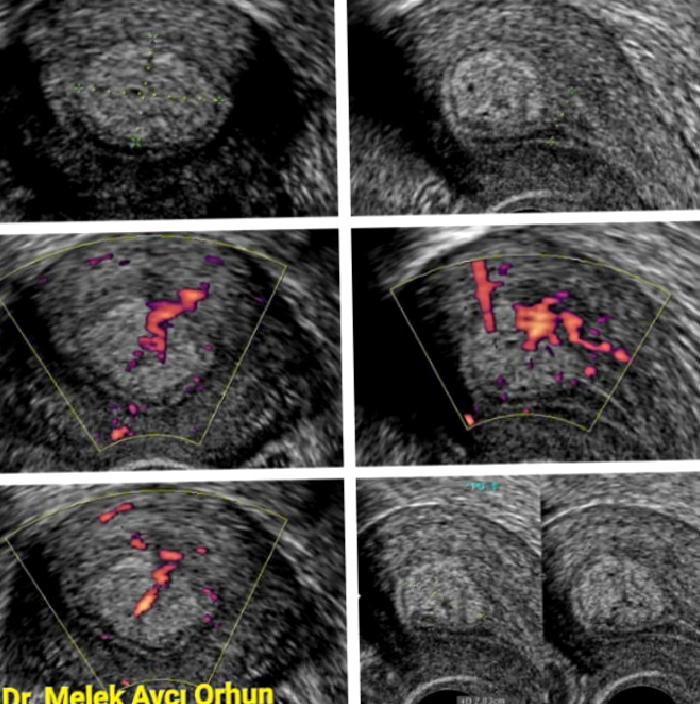

Ultrasonda uterus (rahim) boşluğunu döşeyen endometrium adı verilen dokunun yüzeyinden uterus boşluğuna doğru büyüme gösteren bir veya birden çok yumuşak doku kitlesi şeklinde görülürler. İç yapısı genellikle köken aldığı endometrium tabakası ile benzer özelliklere sahip olup, yuvarlak veya oval şekilli, dış konturları düzgündür.Endometrium dokusuna genellikle ince bir sap ile, bazen de geniş tabanla bağlıdırlar. 1-2 mm’den tüm uterus boşluğunu dolduracak büyüklüklere kadar değişen boyutlarda görülebilirler. Poliplerin çoğunluğu fundustan, bazen de ön veya arka duvar endometrium tabakasından orjin alıp aşağı doğru uzanırlar (Saplı bir üzüm tanesine benzetilebilir). Polip kitlesini besleyen damarlar bu saptan kitle içerisine ağaç dalı gibi uzanım gösterdiğinden renkli Doppler ultrasonile incelenerek sapın orjin aldığı bölge belirlenebilir. Ayrıca polibin kanlanma özelliklerine göre kitlenin büyüme potansiyeli ya da kötü huylu bir kitle olma olasılığı yönünde ipuçları elde edilebilir. Olası diğer lezyonlarla ayrım veya tedavi için yapılacak girişim yöntemini belirlemek amacıyla, kitlenin köken aldığı endometrium ile olan sınırlarının daha iyi görüntülenebilmesi adına yapılabilecek bir diğer inceleme de SİS’dir (salin infüzyon sonografi). Bu incelemede uterus boşluğuna sıvı doldurularak kitlenin sıvı içindeki tüm kenar özellikleri, rahim duvarında köken aldığı alan şekilde görüntülenebilir.